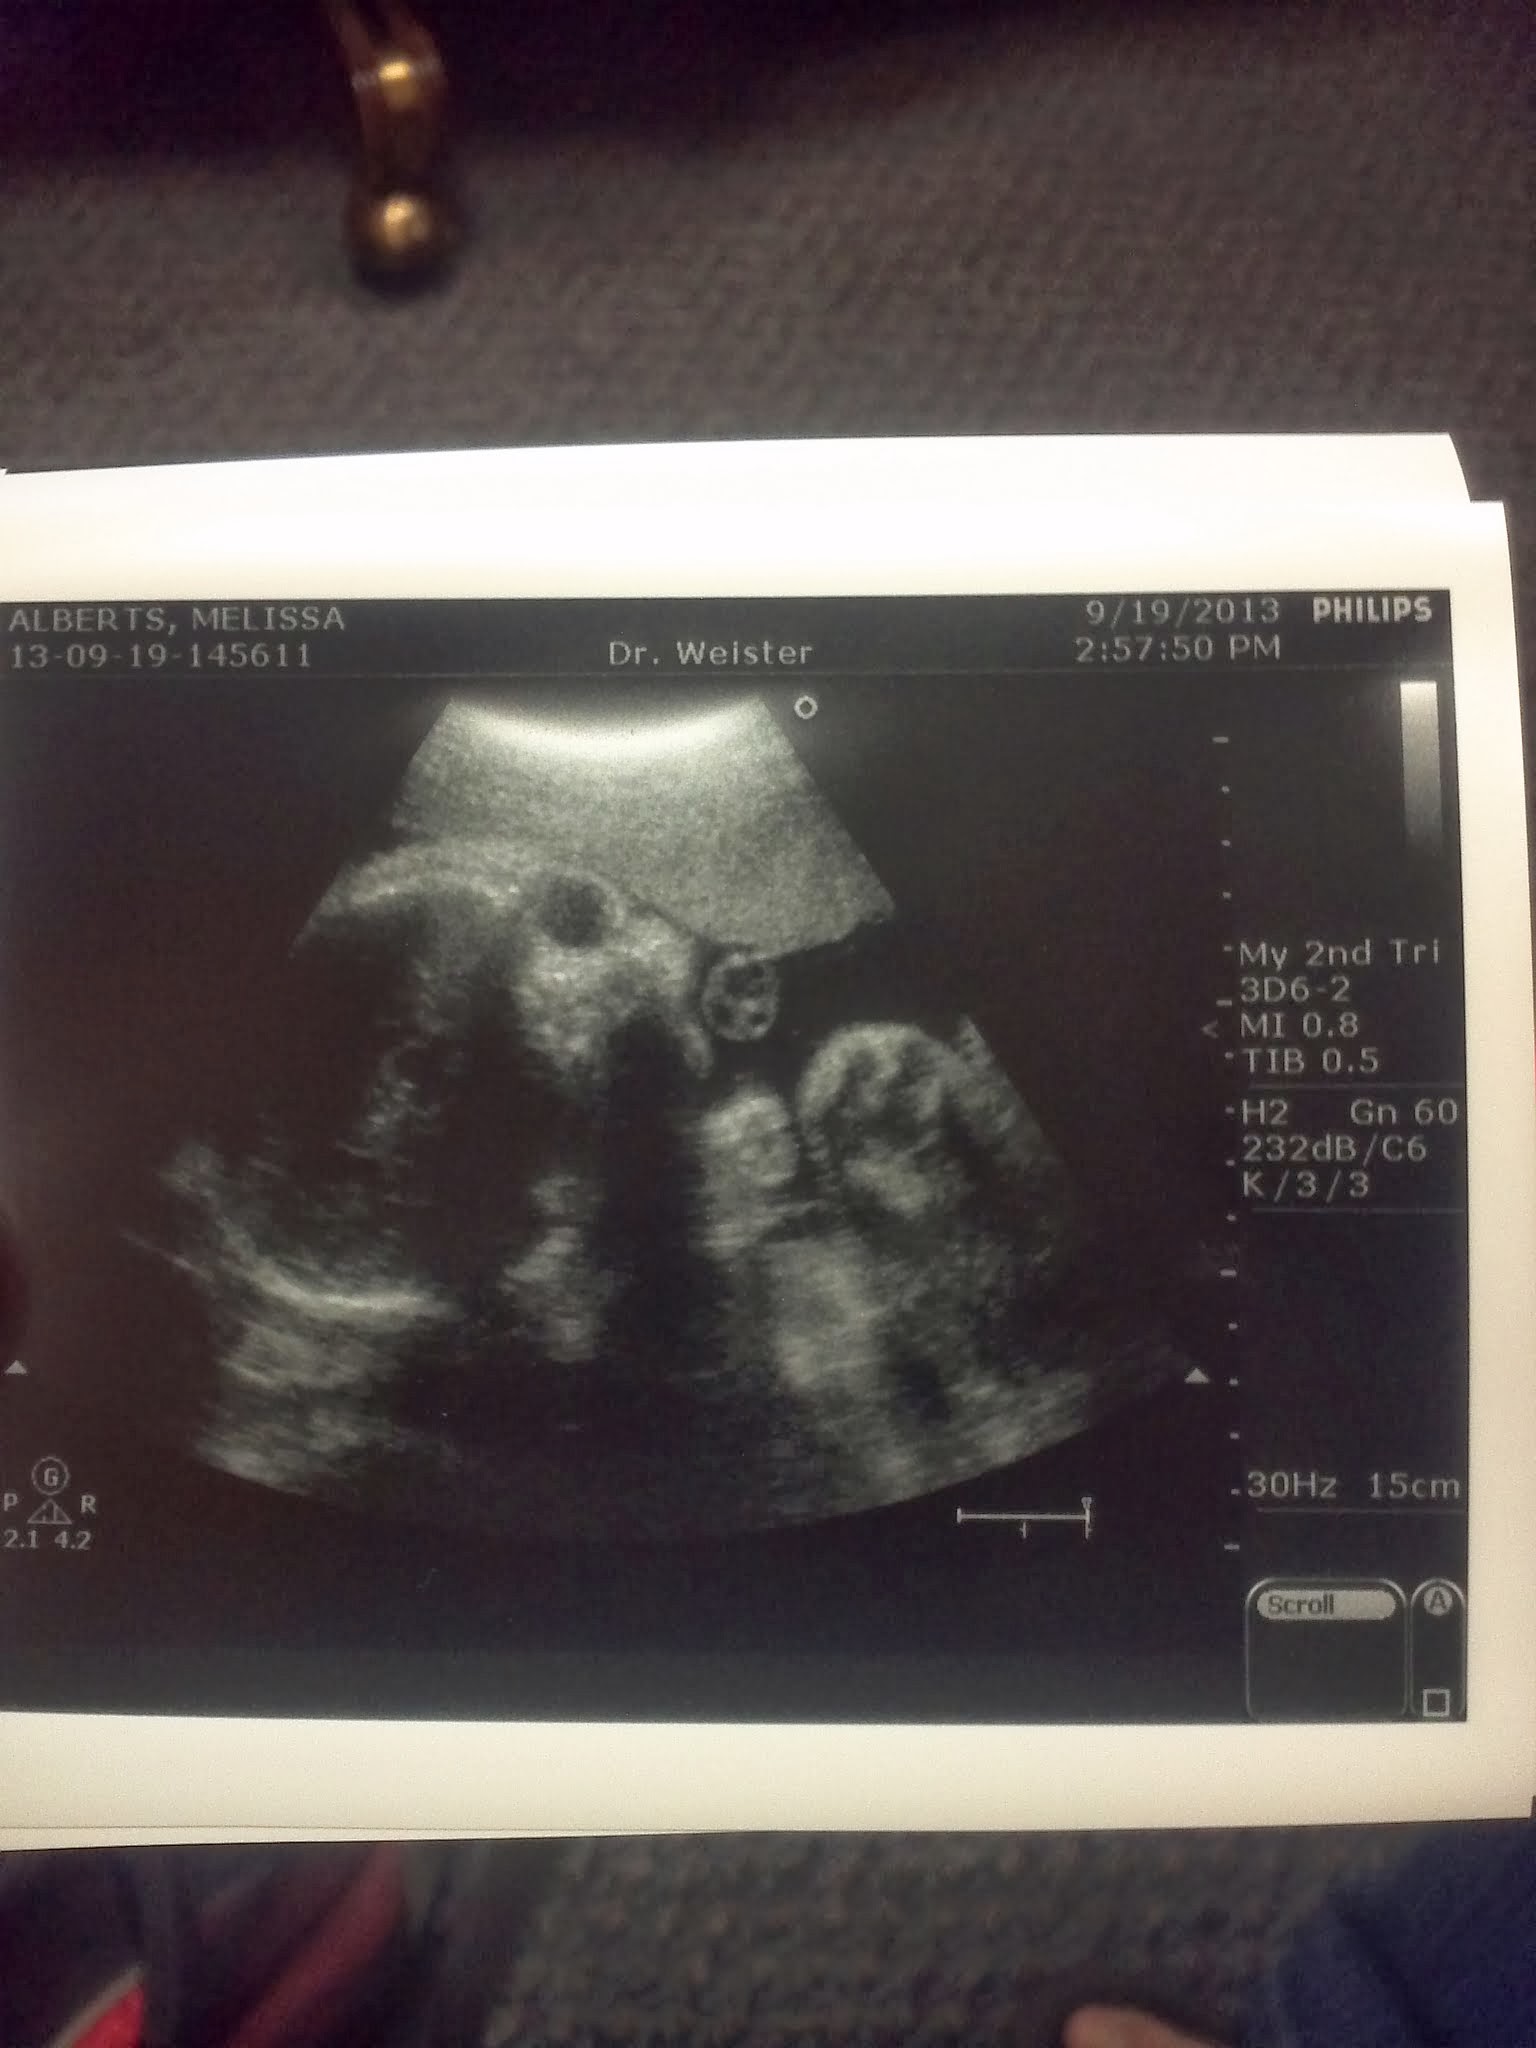

- We also had an ULTRASOUND!!! If you click on one of the pictures you will see the funny description of the way the doctor told us whether it was a girl or boy! He was a nice enough guy but I think he might hate his job… just the vibe we got. It’s either that or the fact that we were in a small room and I haven’t taken my monthly shower :-D.

Loved the bit about “girl parts”! When the ultrasound tech told us Sabin was a boy she used the term “boy bits” every time. I just thought it was kind of funny that they use all the clinical terms for the female anatomy every day but the fetus on the screen has “boy bits”.